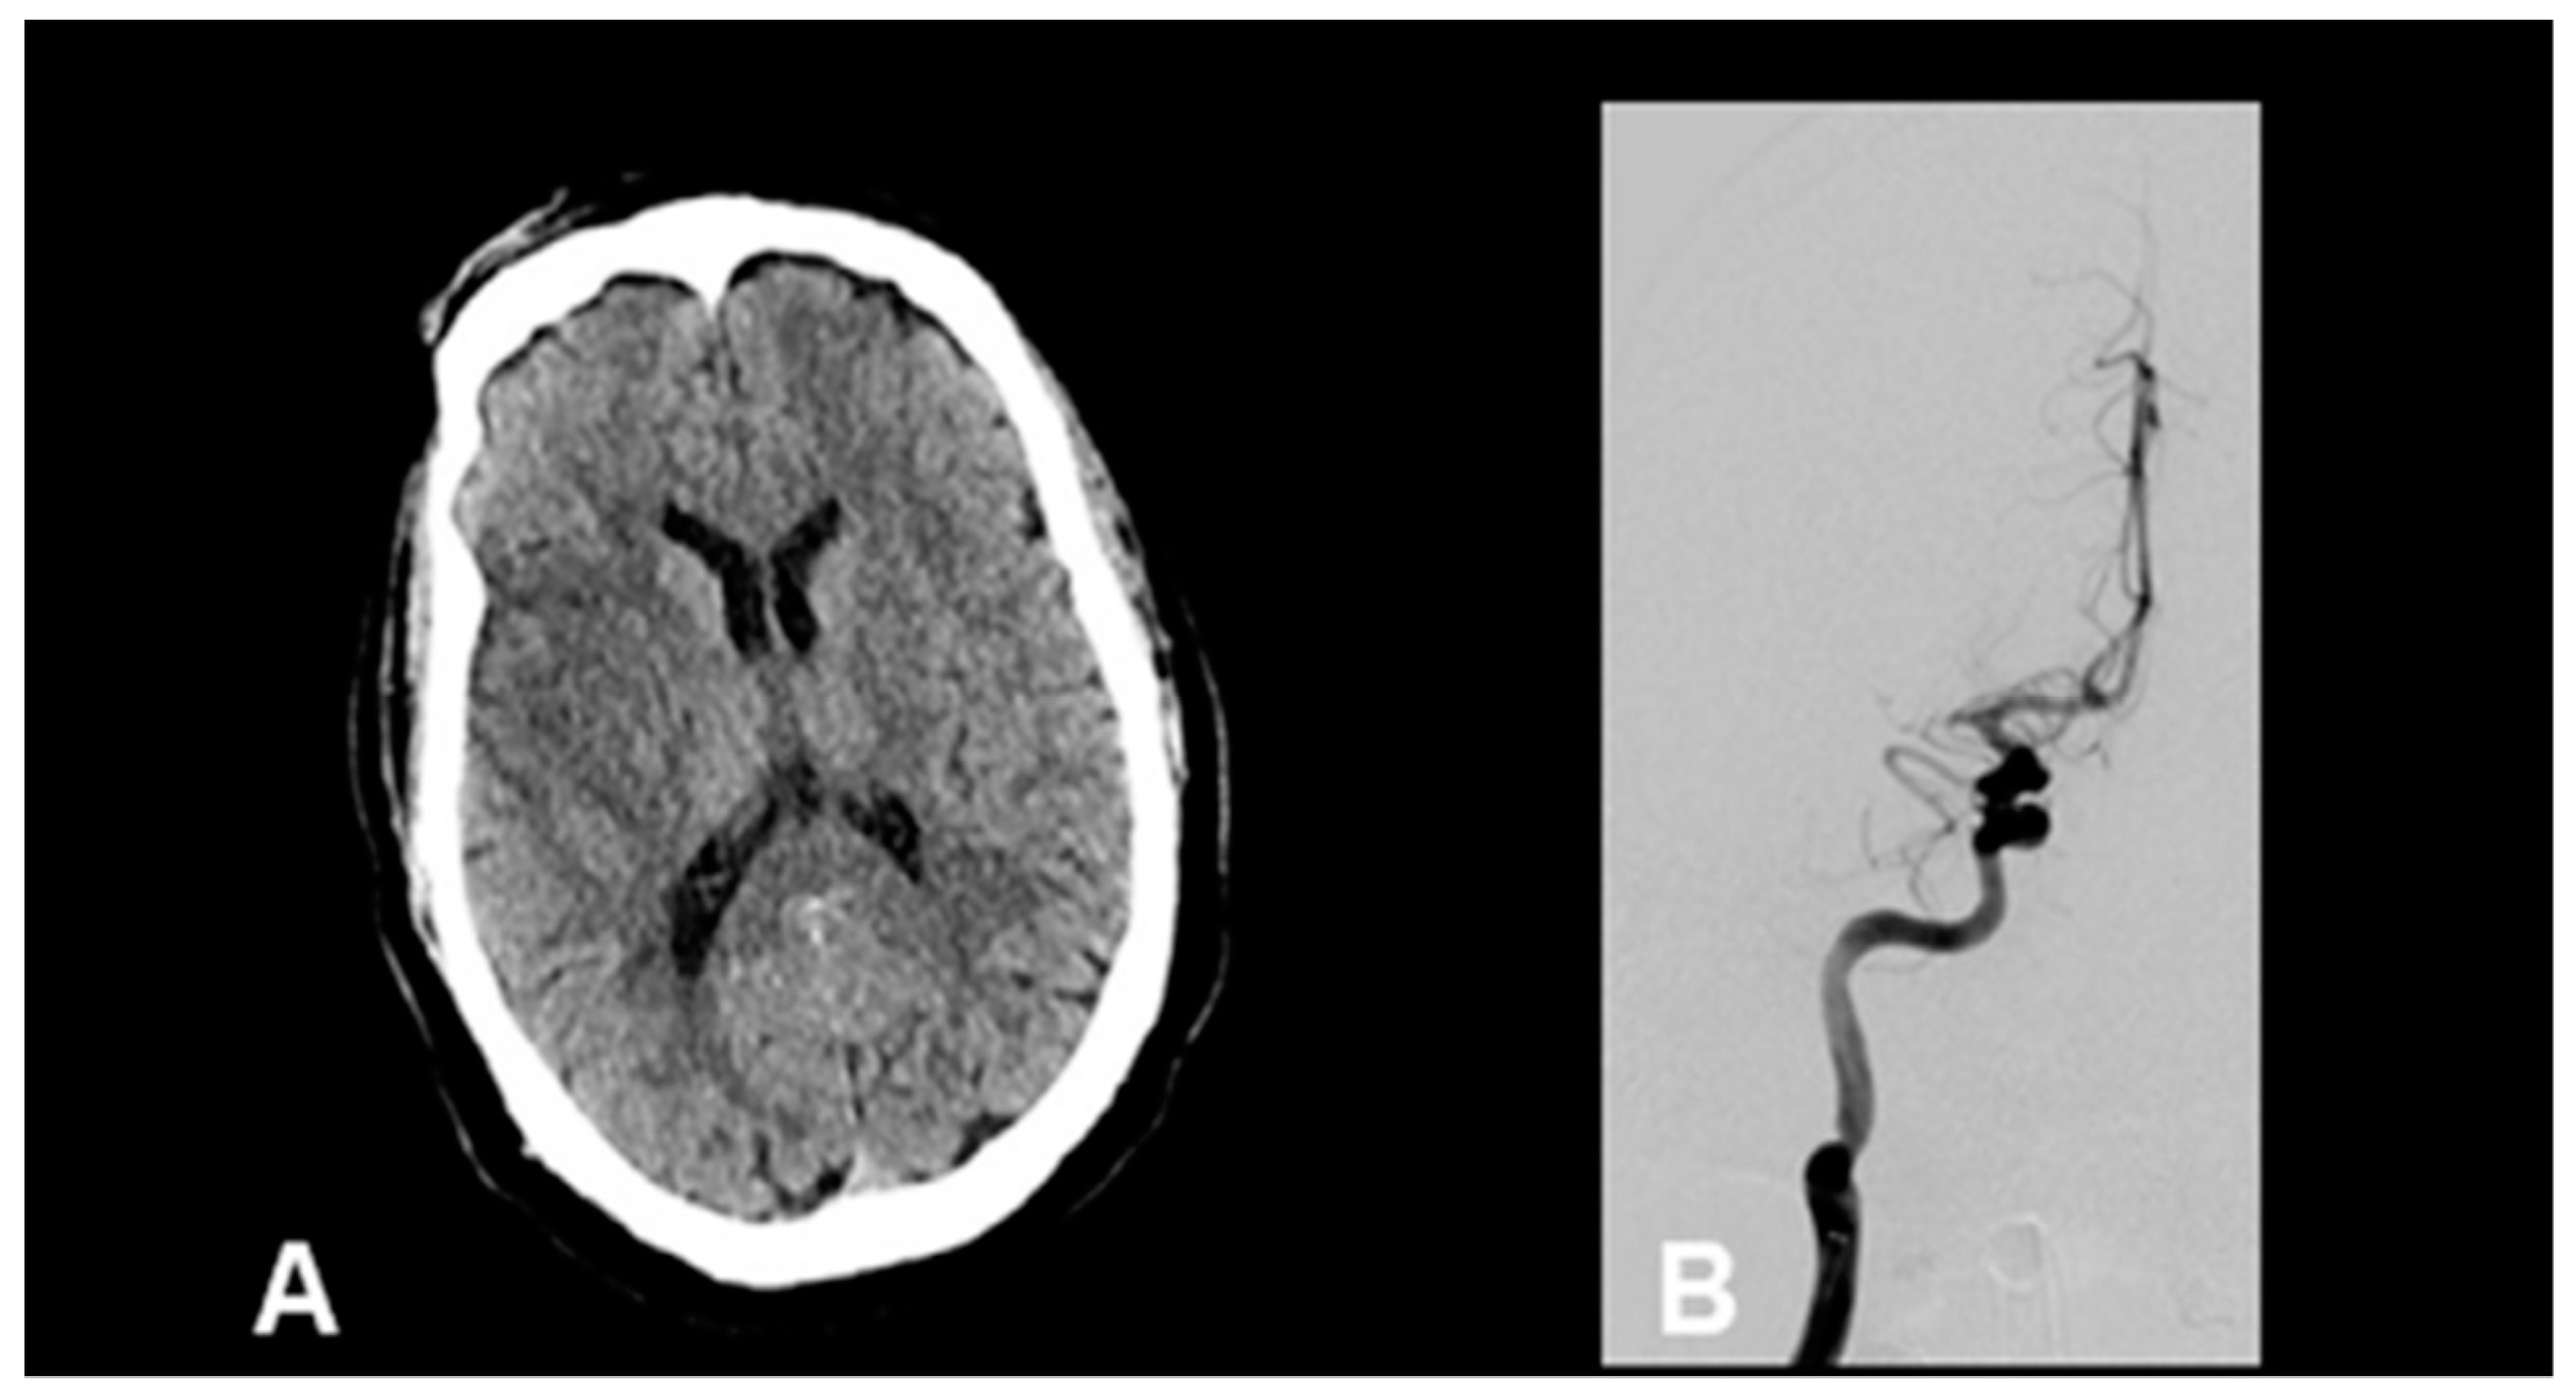

A 66-year-old male with a history of hypertension and asthma initially presented with fevers, chills, nausea, vomiting, and diarrhea. He tested positive for SARS-CoV-2 at that time and was discharged home. Six weeks later, he presented to the hospital with similar symptoms and was hospitalized. On hospital day three, he was noted to have new-onset atrial fibrillation. He was subsequently noted to have acute left hemiparesis with an NIH stroke scale of 15. CT brain showed substantial hypodensity in the right middle cerebral artery (MCA) territory and CT angiography demonstrated a proximal right M1 MCA occlusion (Figure 3A). Additional findings on angiography showed non-calcified atherosclerosis with <10% stenosis of carotid bulbs and a normal aortic arch. The patient was not a candidate for pharmacologic thrombolysis given that recognition of his symptoms was outside the window for treatment, however, CT perfusion suggested a mismatch profile favorable for mechanical thrombectomy. Multiple attempts to recanalize the MCA occlusion were unsuccessful even after the use of eptifibatide infusion and multiple passes with an aspiration catheter (Figure 3B). Transthoracic echocardiography (TTE) was also obtained on day three of admission which showed Left Ventricular Ejection Fraction (LVEF) of 28% (unknown baseline), LV dilation, no shunt, and no thrombus. TTE was repeated on day five of admission which showed LVEF of 19%, severe Right Ventricular (RV) dysfunction, no shunt, and no thrombus. Case reproduced with permission from Batra, A.; Clark, J.R.; LaHaye, K.; Shlobin, N.A.; Hoffman, S.C.; Orban, Z.S.; et al. (2021) [57].

Figure 3.

Representative neuroimaging from a patient with recent SARS-CoV-2 infection, new-onset atrial fibrillation, and proximal right MCA occlusion. (A) Non-contrast head CT reveals areas of hypoattenuation within the right MCA vascular territory. (B) Conventional angiography revealing persistent proximal M1 occlusion. Adapted with permission from Batra, A.; Clark, J.R.; LaHaye, K.; Shlobin, N.A.; Hoffman, S.C.; Orban, Z.S.; et al. (2021) [57].

This case demonstrates several of the proposed mechanisms for acute stroke in those recovering from SARS-CoV-2 infection, namely new-onset cardiac dysfunction with the development of atrial fibrillation and depressed EF in a patient with few pre-existing comorbidities. The development of such cardioembolic stroke mechanisms may partly explain the oversampled number of large vessel occlusions seen in SARS-CoV-2 infection. Additionally, the case illustrates the challenges encountered in the treatment of COVID-19-associated strokes.